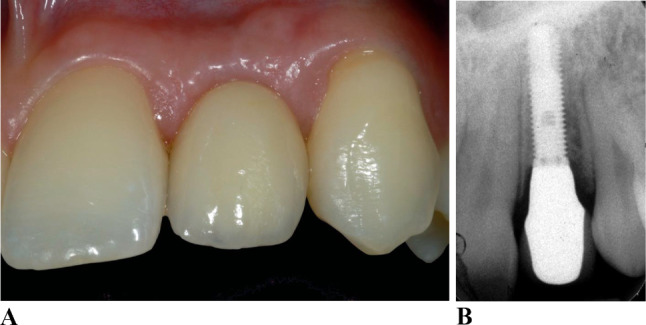

Results: The mean peri-implant crestal bone loss during the first 12 months was 1.3 ± 0.7 mm. Patients with gingival phenotype 1 had a significantly greater rate of increased crestal bone loss at implants (p = 0.016). No significant differences were present in subsequent years. The prevalence of mucositis at all implants was 27.2%, and the prevalence of peri-implantitis 9.3%. Univariate analyses indicated a significantly higher peri-implantitis risk in patients with gingival phenotype 2 (p-OR = 0.001; p-OR = 0.020). The implants of patients with phenotype 2 had significantly greater probing depths (1st year p < 0.001; 3rd year p = 0.016; 10th year p = 0.027; 15th year p < 0.001). Patients with gingival phenotype 3 showed no significantly increased probing depths, signs of inflammation and crestal bone loss.

Abstract Image